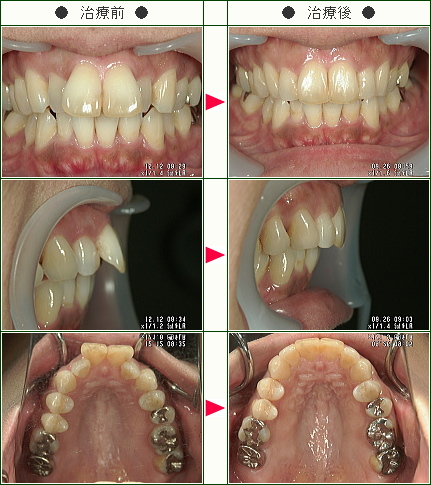

☆出っ歯矯正症例(M.I様 43歳 男性)

治療解説

主訴は前歯の前突感の改善です。

まずはワイヤーを使用してデコボコを改善していきます。

ワイヤーの使用期間が約4か月で、マウスピースを3か月使用して歯並びを内側に傾斜して治療していきました。

トータルでの治療期間は7ヵ月で、調整料金を含めたトータルの治療費は29万円です。

上側だけの部分矯正では、噛み合わせは変わりませんので、見た目の改善だけの審美治療になります。

部分矯正において、ワイヤーでデコボコを改善するだけだと、矯正前よりも少しだけ前方に出てしまうため、歯の隣接面を少し削ることで前歯の前突感を改善していきます。

どこまで前歯を中に入れたいかで、隣接面を削る量は患者様の判断で決まります。

また歯を削らないでデコボコを治すだけですと、デコボコのある間にブラックトライアングルという隙間も残るため、ブラックトライアングルを減らすという目的のためにも前突感を改善するためにもその部分の隣接面を削って内側へ入れていきます。